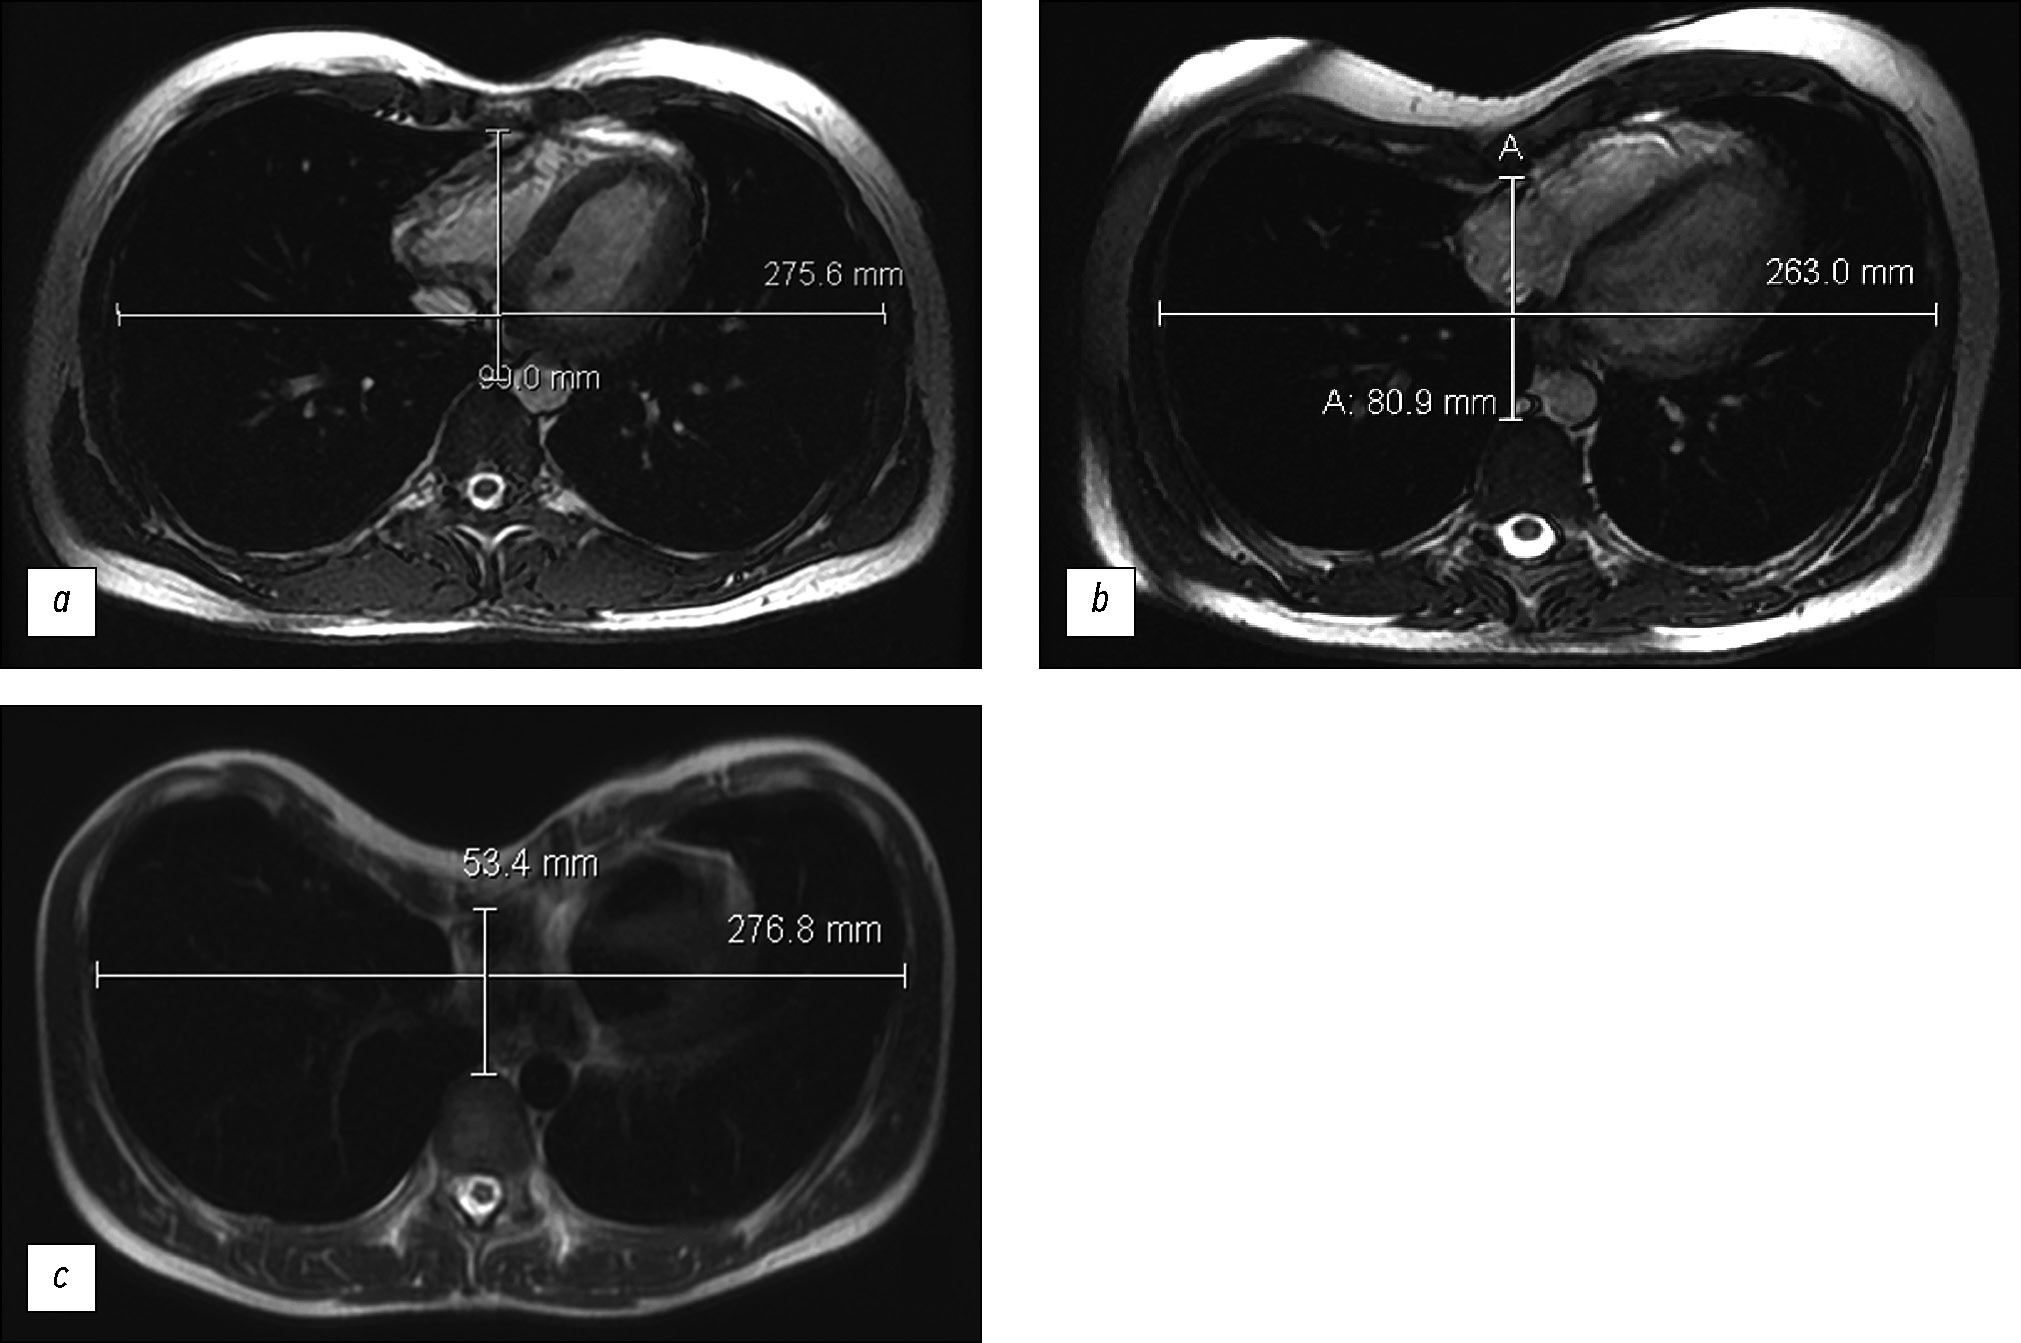

Prospective evaluation of the extensibility of the ascending aorta wall and its vascular prosthesis in a patient with an aneurysm with technically flawless surgical correction and postoperative decrease in functional parameters: A case report

In this clinical case, a patient who had an instrumentally detected aneurysm with the lumen expanding up to 60 mm underwent a surgically flawless prosthetic replacement of the ascending aorta. This treatment led to decreased exercise tolerance, decreased contractile function of the left ventricular myocardium at rest, and enlarged pulmonary artery. The leading factor was a decrease in the volume of systolic expansion of the aorta down to 5 mL (at the initial 13 mL), despite a noticeable increase in the extensibility and a decrease in mechanical stiffness compared with initial indexes of the affected aortic wall. In the literature review, considering mechanical extensibility and elasticity, problems in creating aortic prostheses equivalent to those for healthy biological tissues were discussed.